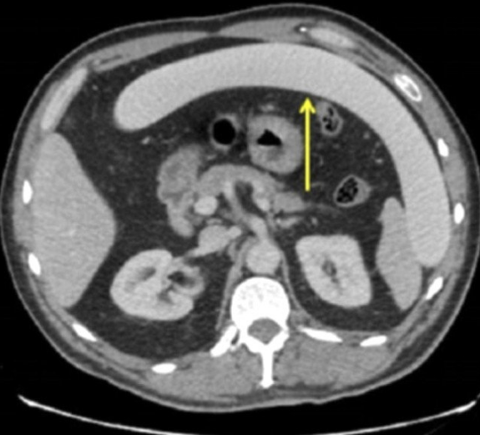

Galerinin tamamı için tıklayınızDaha önce dünyada örneklerini rastlandı ama bu kadarına değil. Birazdan okuyacağını bu haber akıllara durgunluk veriyor. İngiltere'nin Yorkshire bölgesinde bir adam gecenin bir vakti acil servise getirildi. Sürekli bir şeylerden dert yanıyordu ama o kadar sarhoştu ki ne dediği bir türlü anlaşılamıyordu. Doktorlar daha sonra derdinin ne olduğunu anlayınca şoke oldular. İşte akıllara durgunluk veren o olay